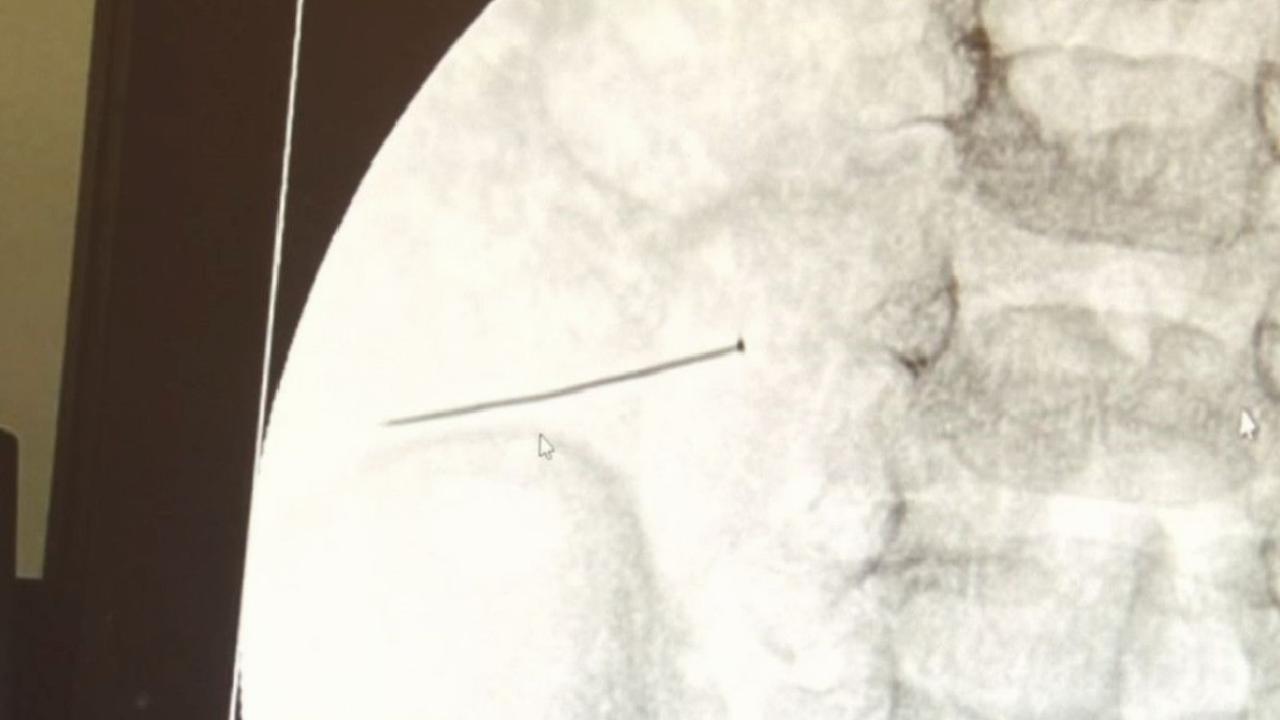

3 SANTİMLİK İĞNE BAĞIRSAĞINI DELDİ

Burada yapılan tetkiklerde 2 yaşındaki çocuğun ince bağırsağında yaklaşık 3 santimlik toplu iğne olduğu ve bağırsağı deldiği belirlendi.

Ertesi gün bağırsakta delinmeyle sonuçlanmış ve çocukta da ciddi semptomlar meydana getirmişti. Bu şekilde hasta bize başvurdu. Tetkikler sonucunda yabancı cismi tespit ettik, semptomları ve bulgularına göre de çocuğu ameliyata aldık. Yaklaşık 3 santim boyunda bir toplu iğnenin ince bağırsağı deldiğini, ince bağırsaktaki içeriğin de karın içerisine dolduğunu gördük. Ameliyatı başarılı bir şekilde tamamladık, yaklaşık 1 saat süren bir ameliyattı" dedi.

Öte yandan, yaklaşık 3 santimlik toplu iğne filme yansıyan görüntüsüyle gözler önüne serildi.